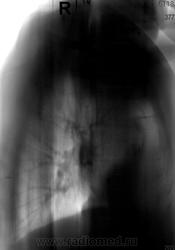

Не ясный...  В клинике превалирует одышка...

Отмечает внезапно возникшую одышку? ЭХО-КГ было? Мне чудится симптом Вестермарка в верхней доле справа и нежная интерстициальная инфильтрация в S6 справа. Хвост правого корня не красивый, может он "обрублен"? Ну и признаки ХОБЛ есть.

Плевральные наложения справа, пока больше ничего плхого не вижу

Тень сердца объясняет причину одышки.

Во-во: аортальный порок опять.

Может, ляпну глупость: а разве есть признаки застоя?

Есть.

Коллеги, а как Вы объясните эту тень? Что-то я на ней зависла. Не ателектаз, не междолевой плеврит. Абдоминомедиастинальная липома?

Понятно. ТЭЛА, конечно, тоже может быть. Но все равно-сердешная

Тень это жир, по прямому тоже хорошо видно что сердце жирновато

Попробую объяснить. Стрелок на картинках не нарисую, по причине что я сейчас однорукая (отдыхаю на больничном со сломаной правой). Я не настаиваю на своем мнении, мне только "почудилось". Если сравнивать лег рисунок верхних долей, то справа он мне кажется обедненным. Для такого-то сердца и сосудов по лег полям должно быть поболее. А интерстиц инфильтрация, потому что нет "пятен" и "хлопьев" сливающейся альвелярной (простите КТ-шный термин), а есть нежное сетчатое затемнение, на фоне которого прослеж сосуды. Вот дисковидных коллапсов я не нашла, покажете?

Насчет ХОБЛ - стенки бронхов утолщены муфтой, хрящевые кольца трахеи, главных, долевых и устьев сегментарных кальцинированы, это отлично видно на линейках.

У такого человека в возрасте мне кажется сейчас важнее всего как раз исключить ТЭЛА, ХОБЛ и застой это меньшее из зол.

Очень важна клиника, ЭХО-КГ, димеры.

Как-то сомневаюсь я в абдоминомедиастинальной липоме. Огроменные размеры, фестончатый контур. Подумала ещё о парастернальной диафрагмальной грыже. Валентин Львович, а в архиве что?